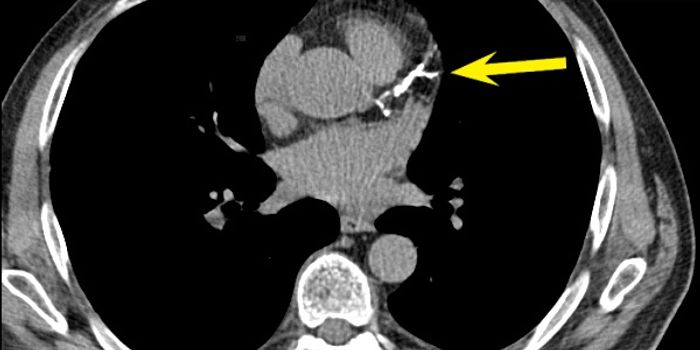

JUN 27, 2016Clinical & Molecular DXComputed tomography (CT) scans can often be life-saving medical procedures, but do we really understand the risks i ...